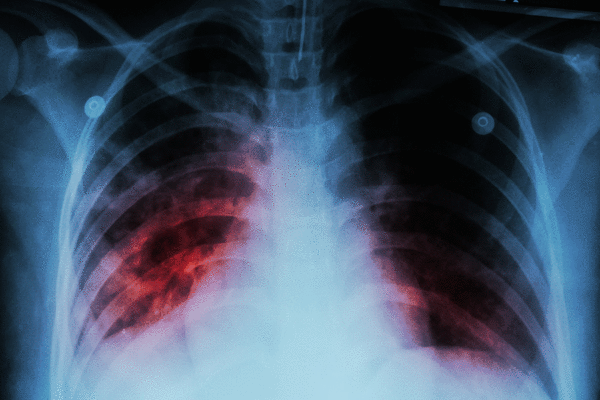

Tuberculosis is a bacterial infection with both active and latent stages. A person with active tuberculosis disease, which can be deadly, can spread the disease. A person with a latent infection can’t, but they can develop the disease at any point.

Consistent, daily antibiotic treatment for four to nine months, with no skipped doses, is crucial to knocking it out. Skipping doses can allow the germs to mutate into drug-resistant TB, which is one reason health agencies spend so much to ensure patients take their medication.